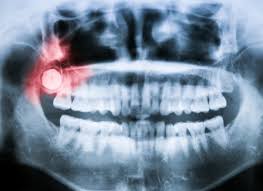

Edge Dental are a Houston city dental care clinic who are available to treat patients with any dental issues they are experiencing. Contact us today by calling (281) 940-6960 to book an appointment with our experienced dentists in Houston, TX. Justin Lai DDS, a Family and Cosmetic Dentist in Houston, is Committed to Offering comprehensive care including dental checkups, cosmetic dentistry, dental implants & orthodontics, for the Whole Family in a Relaxed Environment.